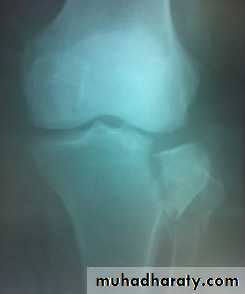

Tibial plateau fractures:Direct blow or fall from height may cause fracture of one tibial condyle or both. Fracture lateral condyle is the commonest named as bumper fracture caused by a force that abducts the tibia upon femur while the foot is fixed on ground. Patient usually is an adult, the knee joint is swollen, bruises, there is diffuse tenderness and doughy feel of haemarthrosis.ligaments injuries must be excluded.

Imaging : X-ray: anteroposterior, lateral & oblique

views. ct -Scan may used to detect amount of depression and comminuation.

Tibial plateau fracture